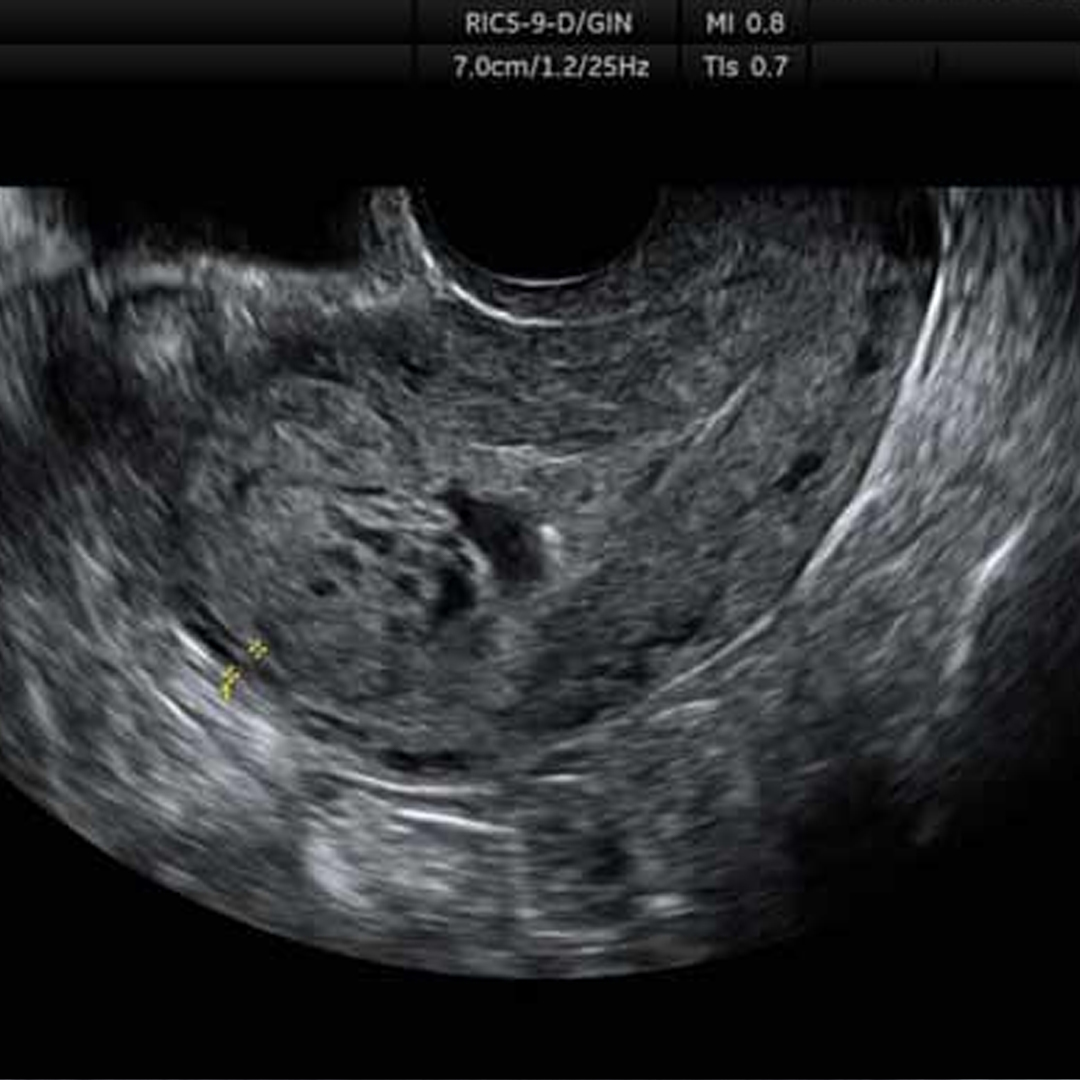

Ecografía Transvaginal

Recomendada en las primeras semanas de embarazo para confirmar gestación e iniciar controles.